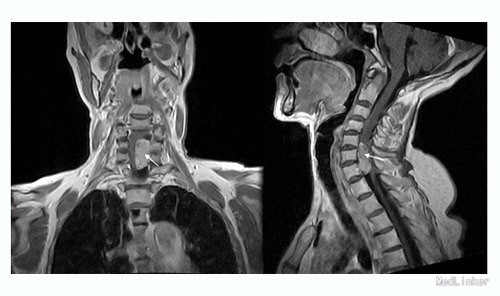

主诉:四肢乏力、蹲下困难2年,加重1月。 病史:患者于2年前无明显诱因出现四肢乏力及蹲下困难,双手支撑地面才能下蹲,无行走困难,无腰部酸痛,无双下肢疼痛、麻木感,大小二便未见异常。患者及家属未予以重视,未行任何诊治。1月前,患者诉四肢乏力及蹲下困难加重,无四肢疼痛、麻木感,大小二便未见异常。遂至外院行MR检查提示:颈6/7水平椎管内蛛网膜囊肿,并相应脊髓圆锥、马尾神经受压移位、聚集。遂收至我科行进一步诊治。患者一般情况较差。

查体:脊柱生理弯曲存在,无明显侧后凸畸形。颈6/7棘突有轻压痛。右侧膝反射未引出(-),左侧膝反射(+),右侧踝反射(+),左侧踝反射(++),双侧踝阵挛、Babinski征(-)。 辅查:肿瘤、生化等均未见明显异常,影像学主要如下:

诊断:颈椎椎管内肿物待查? 治疗:入院后完善相关检查,暂予对症治疗,经治疗组讨论决定,拟行“后路蛛网膜囊肿切除+栓系松解+钉棒内固定术”。